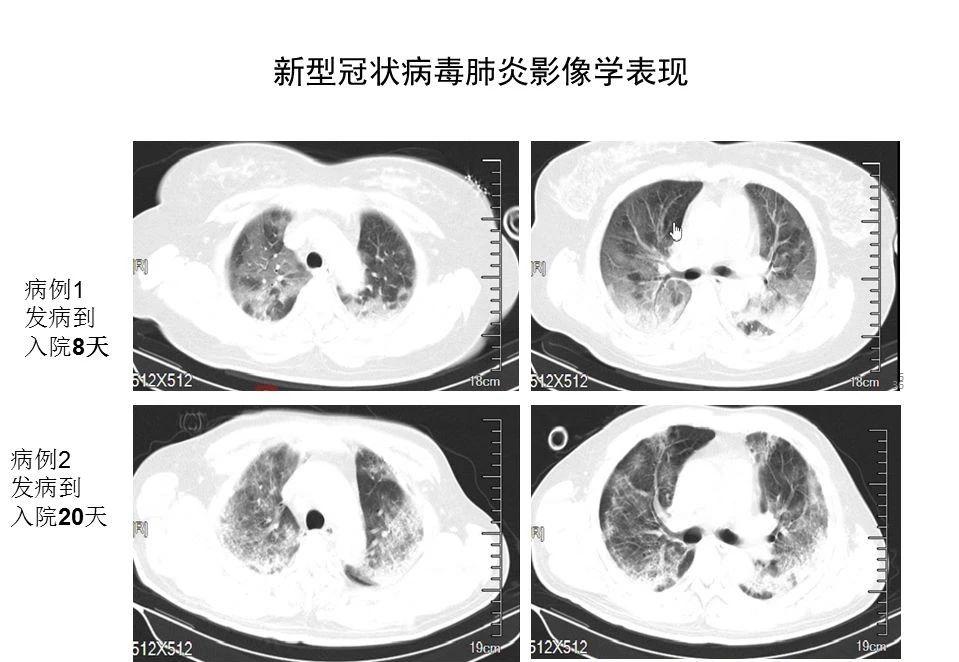

• 早期呈现多发小斑片影及间质改变,以肺外带明显。进而发展为双肺多发磨玻璃影、浸润影,严重者可出现肺实变,胸腔积液少见。

图2. SARI影像学表现(蒋荣猛教授-引自武汉病例)